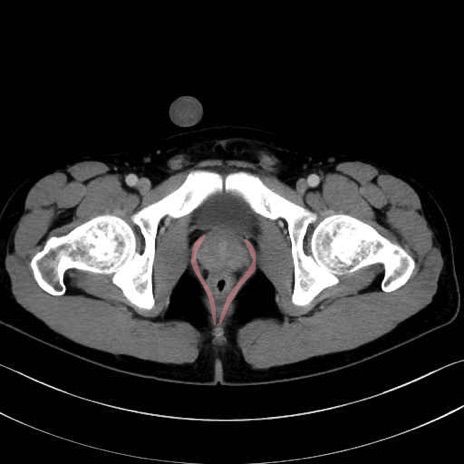

肛門挙筋(levator ani muscle)のCT画像の解剖

肛門挙筋 (Levator ani)